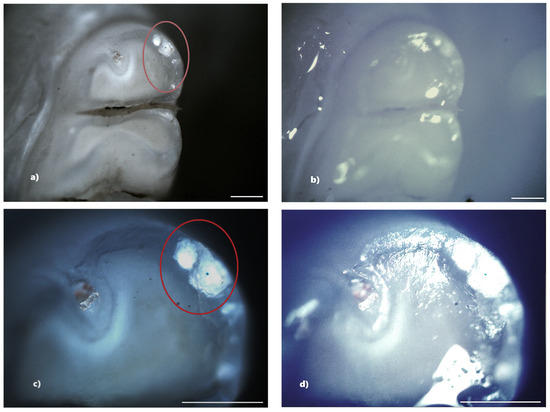

In the standard dose amoxicillin group (50 mg/kg), 10 rats (66.67%) showed at least one clinical form of DDE. Of these, six rats showed hypoplasia, and three rats showed demineralization. One rat showed both clinical forms of DDE. Within this group, out of a total number of 240 teeth, 25 teeth (10.42%) showed at least one clinical form of DDE. Among them, 8 teeth (32%) were incisors and 17 teeth (68%) were molars, and as a clinical form of DDE, 16 teeth (64%) showed hypoplasia (five incisors and eleven molars) and 9 teeth (36%) showed demineralization (three incisors and six molars). Among the 25 teeth with DDE, 12 teeth (48%) presented lesions that were located on two surfaces, thus resulting in a total of 37 tooth surfaces with DDE (Figure 5).

Figure 5. Hypoplasia on the palatal surface of a molar (a—PLM image, cross polarizers, 4× objective; b—BFM image, 4× objective) and on the distal surface of a molar (c—PLM image, cross polarizers, 4× objective; d—BFM image, 4× objective); demineralization on the occlusal surface of 2 molars (e,g—PLM image, cross polarizers, 4× objective; f,h—BFM image, 4× objective). Scale bar represents 500 μm.